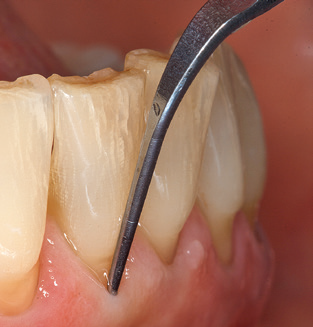

The current working concept for SPT

Good illumination of the working field facilitates the process considerably. The system used by the authors achieves this thanks to a 5x LED ring integrated in the handpiece. Naturally, a range of working tips for different indications is also offered. A straight, universally employable tip is the basic instrument required for machine cleaning of natural teeth (Fig. 5a and b). Curved tips, which allow access to exposed furcations, are also available for hard-to-reach areas in the posterior region (Fig. 6).